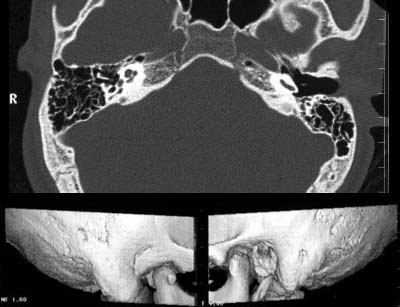

Patient mit seit Jahren bestehender Hörminderung links.

Klinisch auf der rechten Seite kein Gehörgang erkennbar und Dysplasie

der Ohrmuschel. Links normale Verhältnisse.

Links

kommt ein normaler

äußerer Gehörgang zur Darstellung. Auf der rechten Seite kommt anstelle

eines äußeren Gehörganges nur eine knöcherne

Einsenkung zur Darstellung.

In den 3D-Reformationen stellt sich anatomisch links ein normaler

und anatomisch rechts ein aplastischer

äußerer Gehörgang dar.

DIAGNOSE:

Äüßere

Gehörgangsaplasie